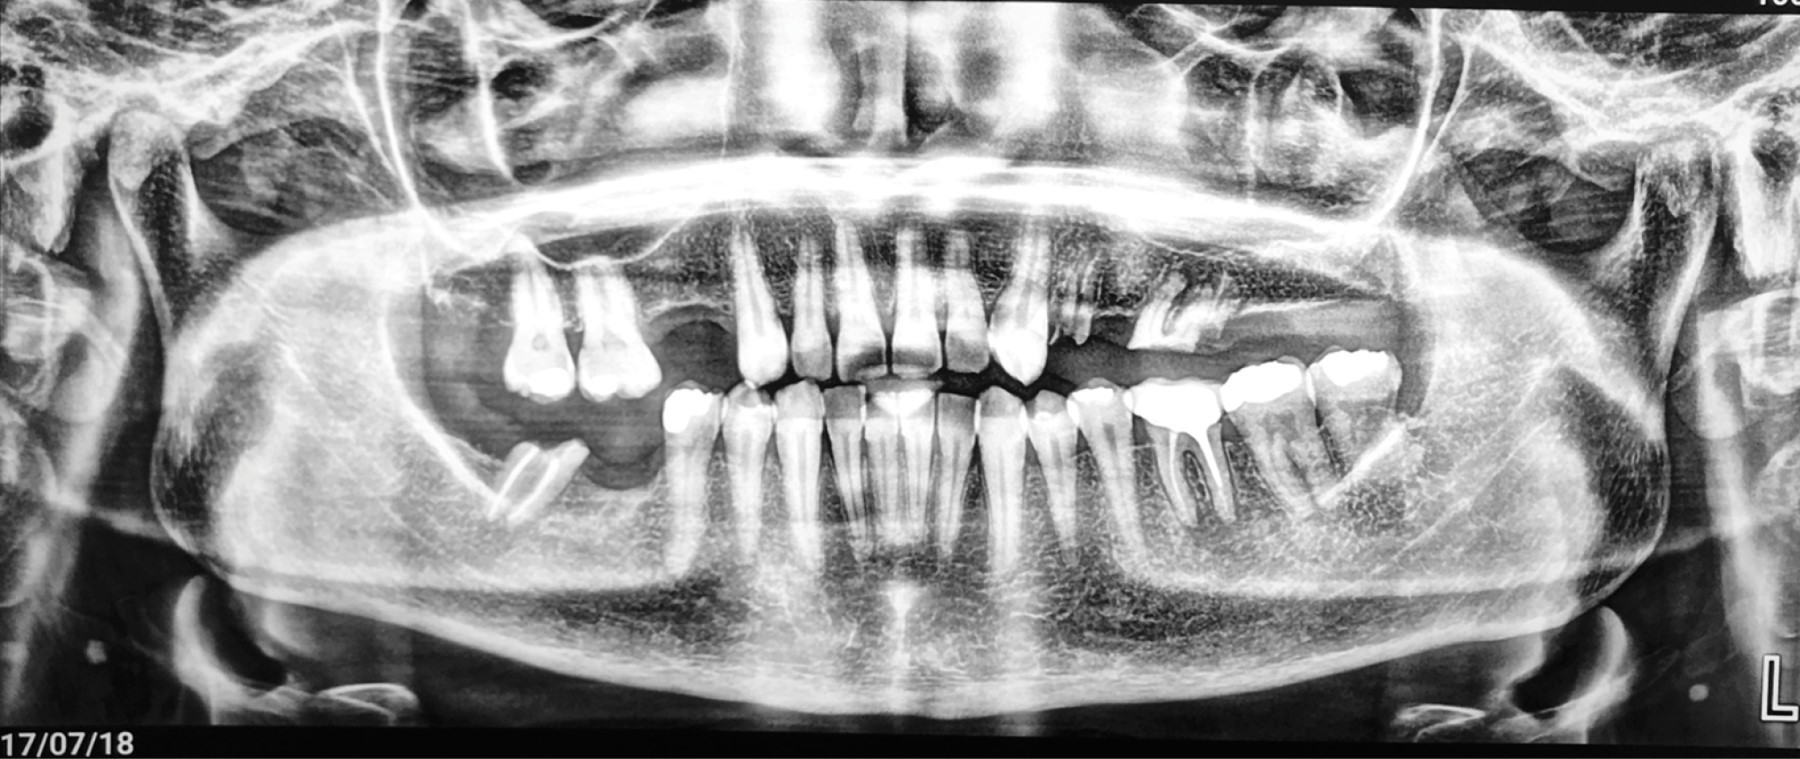

La radiografía panorámica no mostró con claridad la lesión (Figura 2).

Figura 2